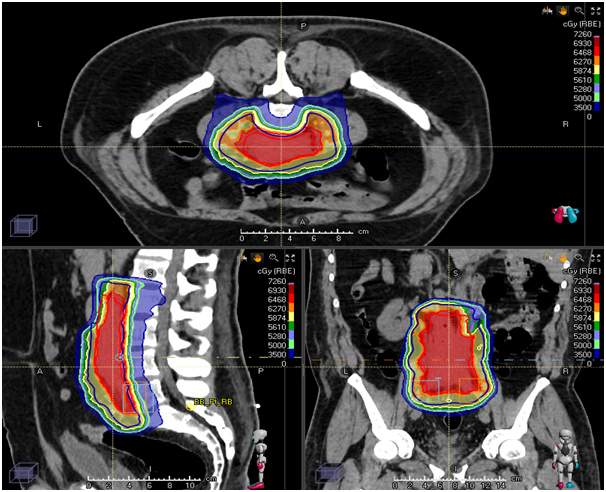

Proton therapy for Soft-tissue Sarcomas

Proton-beam RT is a treatment modality that has been used for the treatment of skull base and Para spinal sarcomas and is being increasingly used for STS in other locations. The use of protons, rather than the photons used in conventional RT, has the potential to allow substantial dose reductions to adjacent normal tissues. As with IMRT, this modality may be of particular benefit in patients with the retroperitoneal disease, given the adjacent vital structures.